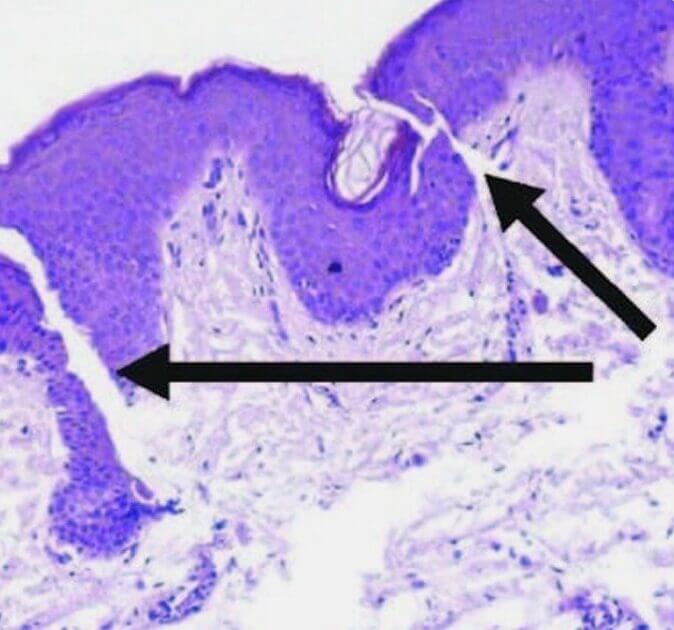

Hypopigmentierte Flecken

Hypopigmentierte Flecken entstehen, wenn pigmentproduzierende Zellen (Melanozyten) absterben oder die Melaninproduktion einstellen.

Die betroffenen Hautstellen werden heller oder weiß. Es ist unklar, was genau zum Ausfall oder Absterben dieser Pigmentzellen führt.

- Die Aktivierung, Migration und/oder Proliferation von Melanozyten in hypopigmentierte Bereiche an der dermoepidermalen Junktionszone (DEJ) soll induziert werden. Diese oberflächliche Dermis stellt die Zieltiefe dar.

- Darüber hinaus stimuliert ein mechanisches Trauma die Migration der Melanozyten von den pigmentierten Bereichen zu den unpigmentierten Bereichen.

- Durch Mikroneedling kann die Anzahl der Pigmentzellen erhöht und die Pigmentproduktion angeregt werden.